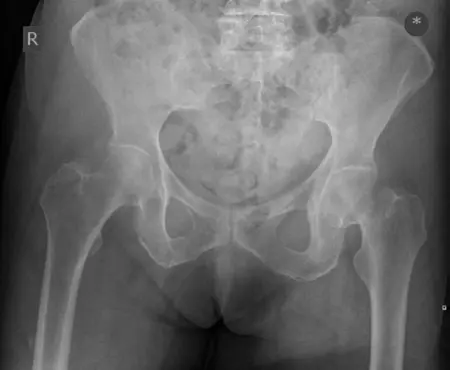

تُعد إصابات وكسور الطرف السفلي من الحالات الشائعة التي يمكن أن تؤثر بشكل كبير على جودة حياة الفرد، حيث تحد من القدرة على الحركة والمشاركة في الأنشطة اليومية. يمتد الطرف السفلي ليشمل منطقة الورك، الفخذ، الركبة، الساق، الكاحل، والقدم، وكل جزء منها معرض لأنواع مختلفة من الإصابات والكسور نتيجة للحوادث، السقطات، الإصابات الرياضية، أو حتى الإجهاد المتكرر.

- مفصل الورك: يربط عظم الفخذ بالحوض، ويسمح بحركة واسعة النطاق.

- حوادث السيارات والدراجات النارية: غالبًا ما تؤدي إلى كسور معقدة في الفخذ، الساق، والورك، مثل كسور التجويف الحقي (Acetabular fractures) وكسور عظم الساق (Tibial shaft fractures) وكسور الرضفة.

- السقوط من ارتفاعات عالية: يمكن أن يسبب كسورًا في العقب (Calcaneal fractures)، كسور البيلون (Pilon fractures) في الكاحل، وكسور العمود الفقري المصاحبة.

- السقوط في المنزل: شائع لدى كبار السن، ويؤدي غالبًا إلى كسور الورك (كسور عنق الفخذ، كسور ما بين المدورين) وكسور الكاحل.

الأشعة السينية (X-rays):

- الفحص الأولي والأكثر شيوعًا لتشخيص الكسور.

- تُؤخذ صور من زوايا متعددة (أمامية، جانبية، مائلة) لتقييم الكسر بدقة.

- في بعض الحالات، قد تكون هناك حاجة لأشعة سينية تحمل الوزن (Weight-bearing X-rays) لتقييم استقرار بعض الإصابات مثل إصابات ليزفرانك في القدم.

- ضروري لتقييم الكسور المعقدة، خاصة تلك التي تشمل المفاصل، مثل كسور التجويف الحقي، كسور هضبة الظنبوب (Tibial Plateau fractures)، كسور البيلون، وكسور العقب.